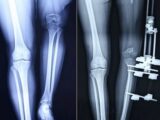

画像は、「Daily Mail」より「チョッパーのあばずれ」としっかり彫られています。この名前の入った部分に、タトゥーショップなどで近頃用いられている皮膚の感覚を鈍くさせるスプレーを使った後、外科用のメスでタトゥーの部分を長方形に切り取り、毛抜きでつまんでビンに入れました。時間にして90分程度だったようです。